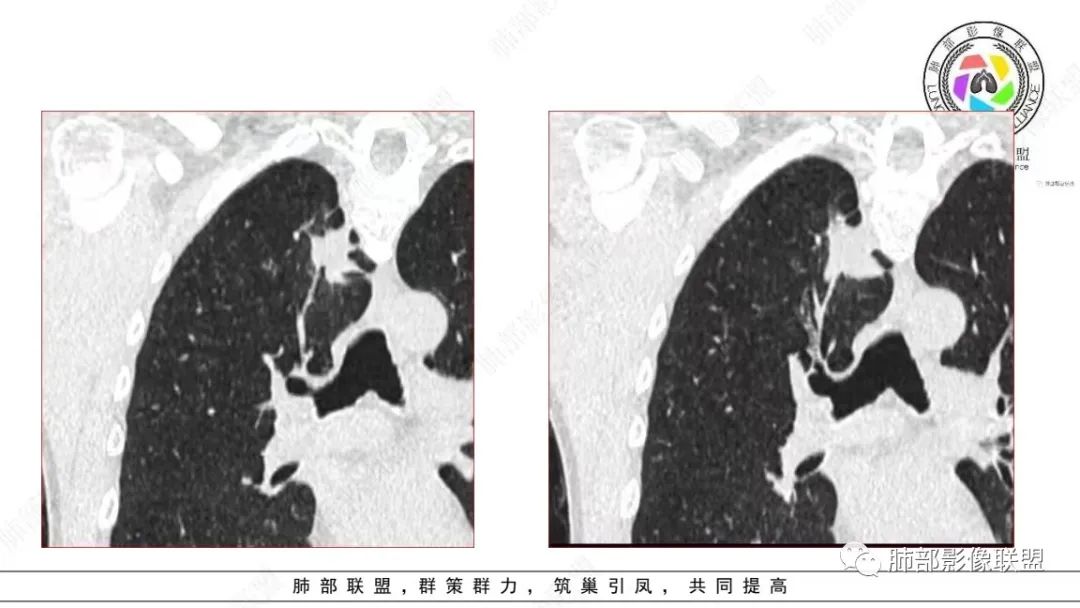

还是和病变成分有关。在肿瘤当中,或者上皮间质转换比较明显等,可以有不同的强化方式。当然也可以表现为延迟强化,可以动脉期明显强化。和肿瘤的具体类型,以及具体病变的病理成分有关。多层面观察,病变是明确有细支气管进入的,而且明确的有铸型的低密度粘液栓。

总结一下:肺内,周围型病变,含有黏液/纤维的,有收缩力的,支气管进入,有粘液栓形成的病变。常见疾病谱当然就是腺癌、特别是结节型的黏液腺癌,还有一些非特异性的慢性炎、结核等。容易形成支气管粘液栓的病变很多,慢性病变中,除了非特异性感染,一些细菌,比较常见的就是结核、曲霉。但是,支气管进入,有粘液栓形成的,周围型,肿瘤性病变,却少之又少。疾病谱中,最常见的就是气管腔内占位,以远粘液栓是继发改变。比如鳞癌、类癌。

在细支气管腺瘤的文献中,病例较少,没有看到过提到有粘液栓形成的病例描述。细支气管腺瘤的病理要点中,1,可以见到细支气管进入病灶。2.双层细胞。细支气管水平的病变,当然就可以有纤毛,有可以分泌黏液的细胞。在细支气管腺瘤中,形成的粘液,可以弥散在组织间隙,也可以聚集,形成粘液湖。更容易经过细支气管排出,形成空洞。类似于腺癌的空泡。这个病例虽然有延迟强化,收缩力比较强,也有支气管粘液栓,但是比较难解释这么低密度的,有延迟强化的,可疑粘液成分。

这个病例还可以深挖,图像有点少,我感觉部分层面可疑少许磨玻璃。最难鉴别的是结节型黏液腺癌,特别是细支气管腺瘤的收缩力比较弱的时候。这个病例收缩力太强,结节型黏液腺癌不太好解释。结合病理及影像表现,这个病例最终诊断:倾向于细支气管腺瘤、合并一些非特异性的感染、支气管内粘液栓形成。细支气管腺瘤,疑难。实性的细支气管腺瘤,更疑难。再合并感染,难上加难。不讲理的一个病例。